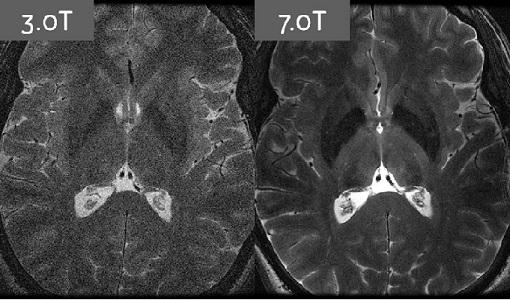

Зигфрид  Траттниг,  врач,  профессор,  основатель  и  председатель магнитно­резонансного  научно­инновационного  центра  (MR  Center  of Excellence  –  MRCE  в  Вене,  Австрия)  считает,  что  7Т  –  это  будущее, благодаря  превосходному  соотношению  сигнал­шум,  спектрального  и пространственного разрешения по сравнению с 1,5 Т и 3 Т системами.

Несмотря  на  то,  что  относительно  мало  научных  исследований намеренно  сравнивали  1,5Т,  3Т  и  7Т,  важно  помнить,  что  высокая напряженность  поля  не  гарантирует  лучшей  диагностической  точности  для всех видов аномалий и заболеваний. Это значит, что 7 Т МРТ занимает узкое место  на  рынке  для  определенных  режимов  и  методов  визуализации.  Они включают 31Р МР спектроскопию (31Р­МРС), которую можно применять как неинвазивный  метод  для  измерения  относительных  внутриклеточных концентраций нескольких фосфорных метаболитов в различных органах.